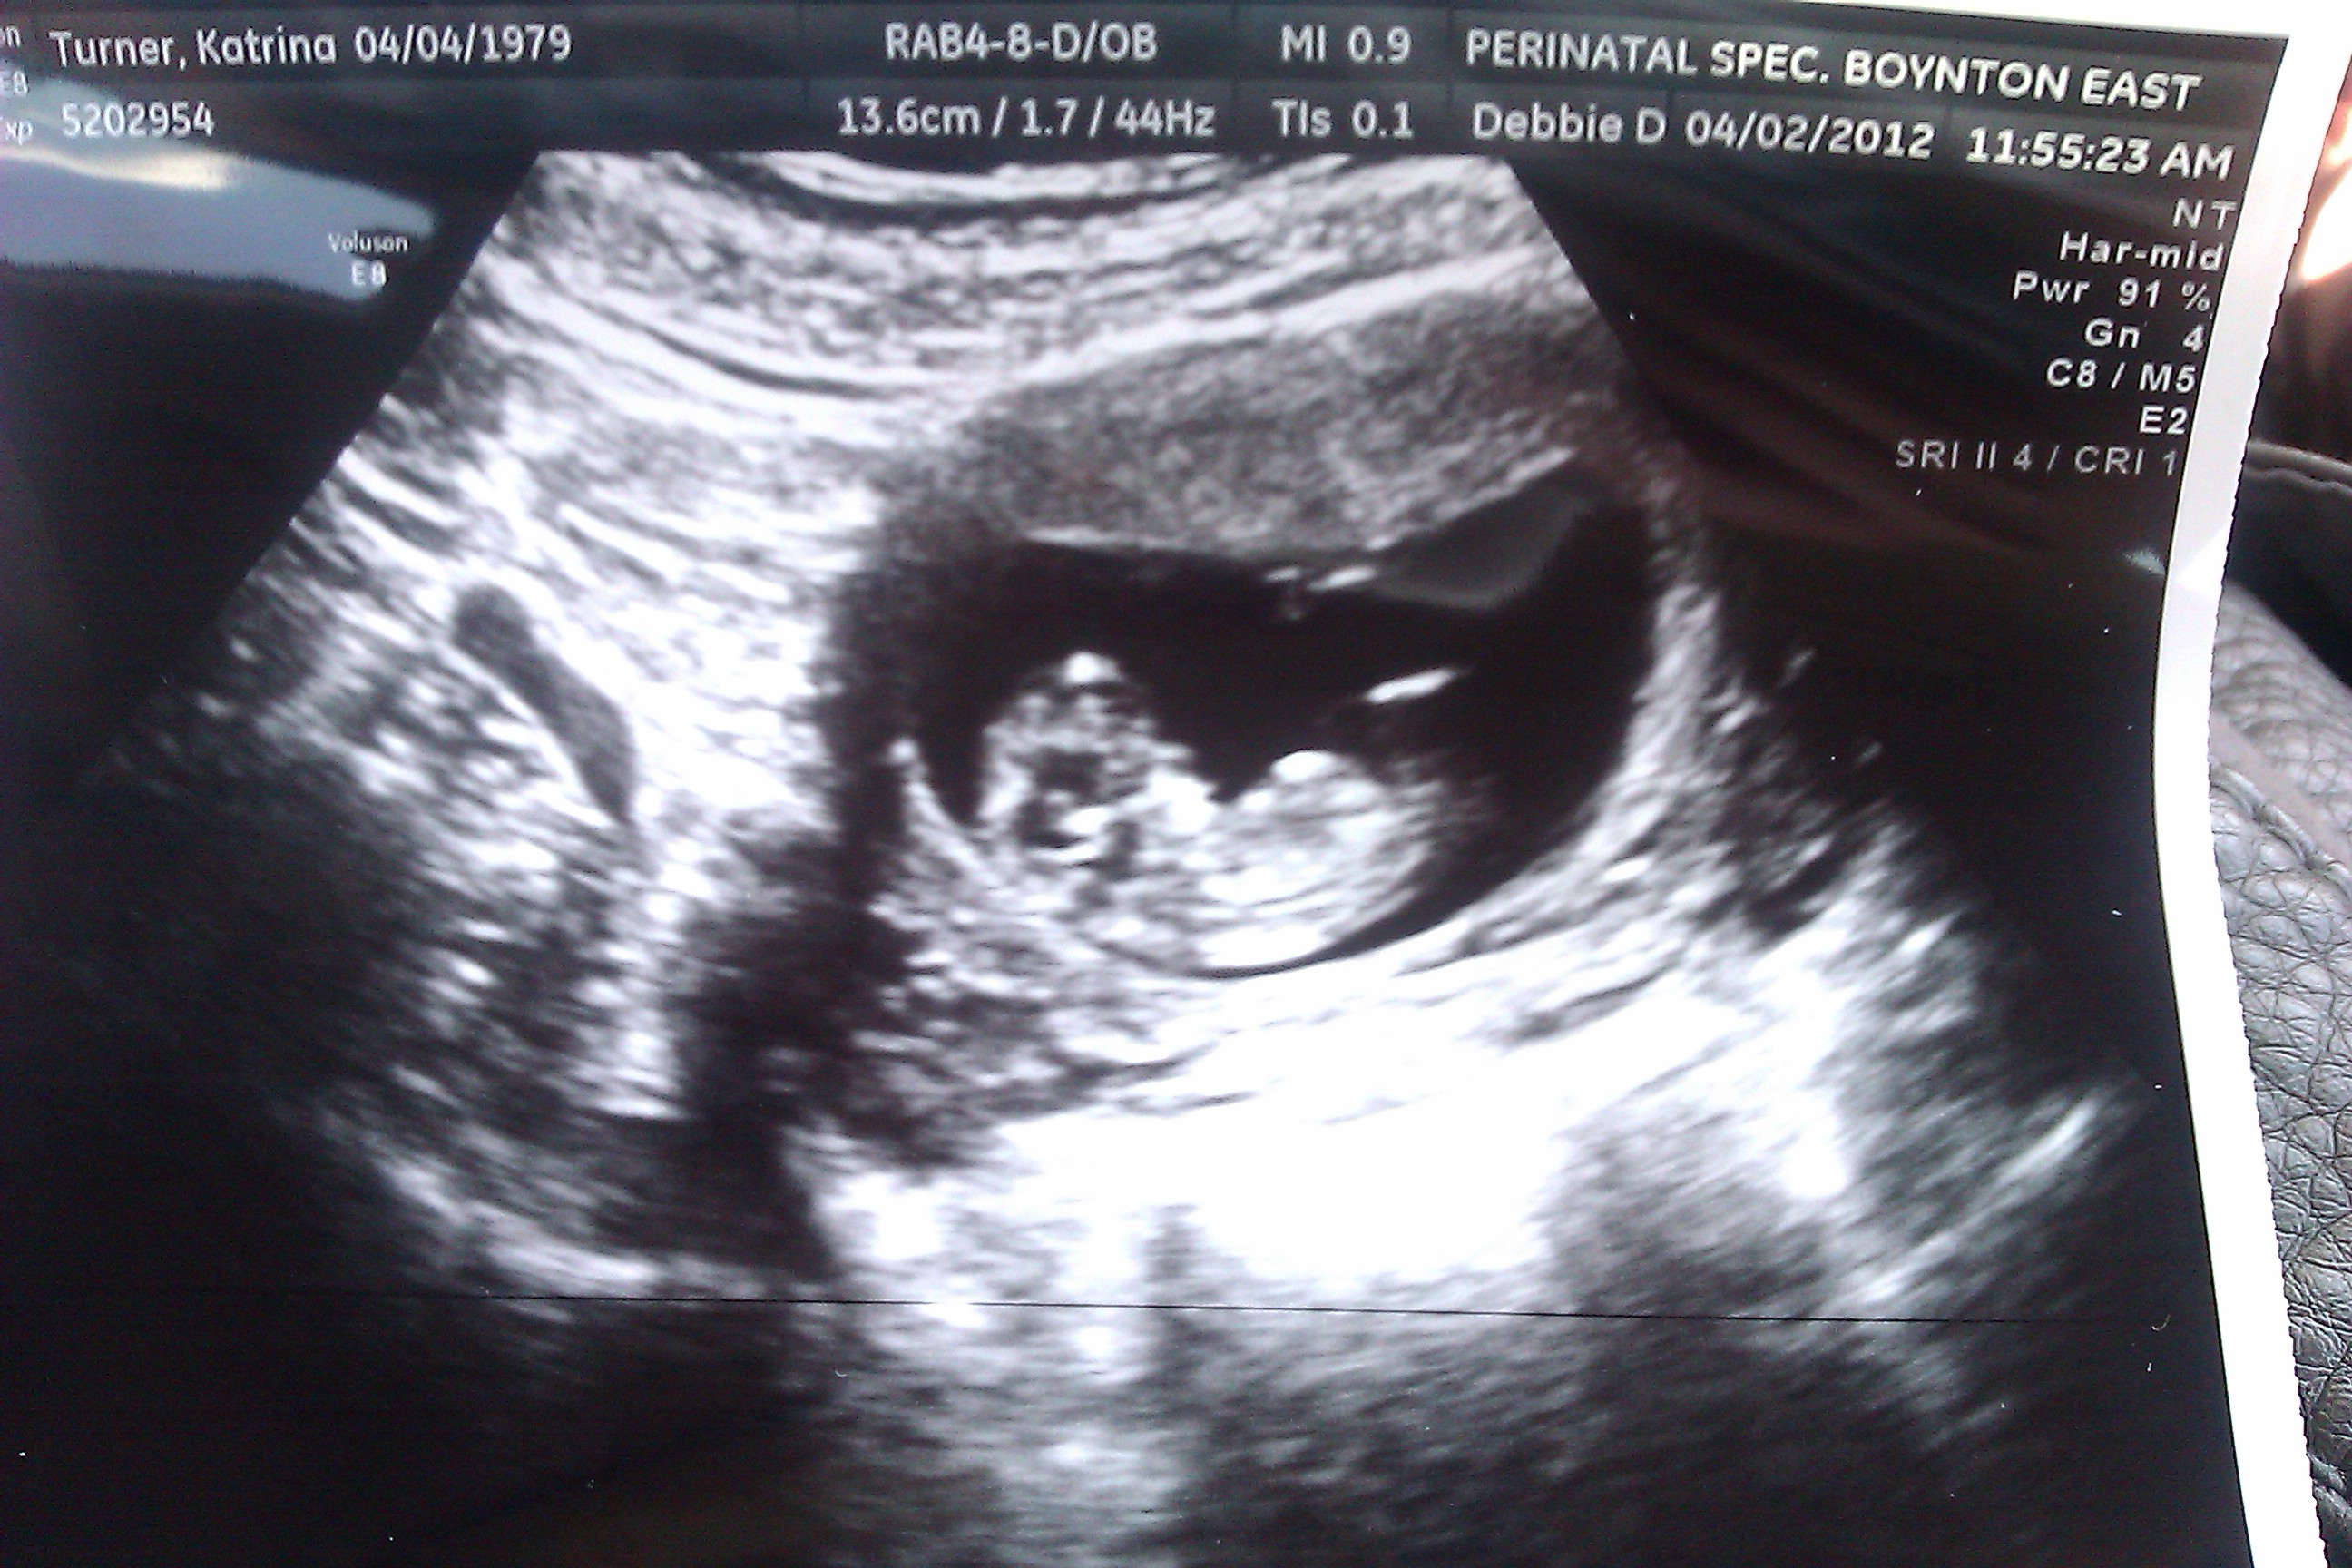

When I asked the ultrasound lady how far along I was, she said about ten weeks. I smacked my mom on the arm and said “See I told you it was that guy. You owe me ten bucks.”

If I’m still up at 2am and I get hungry, it’s okay to eat right? Because technically that’s way before 9pm. And at three months I am eating for two. Well, one and a jelly bean. It’s a really hungry jelly bean.

Hungry Jelly Bean!